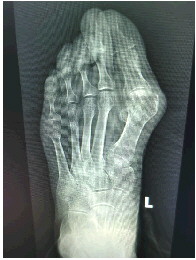

术前影像

77岁的张女士两年前无明显诱因出现左足 趾疼痛,行走后疼痛加重。经对症药物治疗后,症状一度减轻,但未能根治。今年3月,她的左 趾疼痛再度加重,严重影响日常生活,且左足 趾外侧长出“鸡眼”,遂来济阳区人民医院就诊。门诊经检查诊断为“左足 外翻”,收治入四肢显微外科(骨外三科)进一步治疗。入院后,定于次日为张女士实施 外翻矫形术。

术中,于硬膜外麻醉下手术医生依托精密动力系统,分别在其左足第1跖趾关节外侧、第1跖骨远端内侧做长约0.5厘米和2.5厘米的纵行切口,沿第1跖骨颈截骨,于近端髓腔置入一枚 外翻远端板予以固定。手术过程顺利,患者术后第2天即可下地行走。